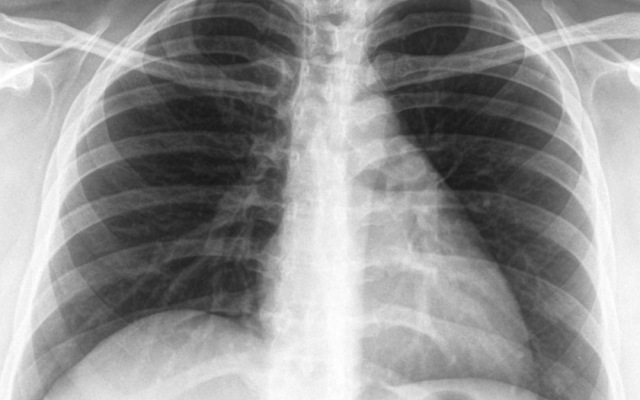

Започва Седмица на отворените врати за туберкулоза, съобщиха на сайта си от Столичната регионална здравна инспекция. Днес се отбелязва Световният ден за борба с туберкулозата.Инициативата е в рамките на изпълнението на Националната програма за превенция и контрол на туберкулозата в България, а целта е да се повиши обществената информираност по отношение на заболяването.До 27 март 2026 г….